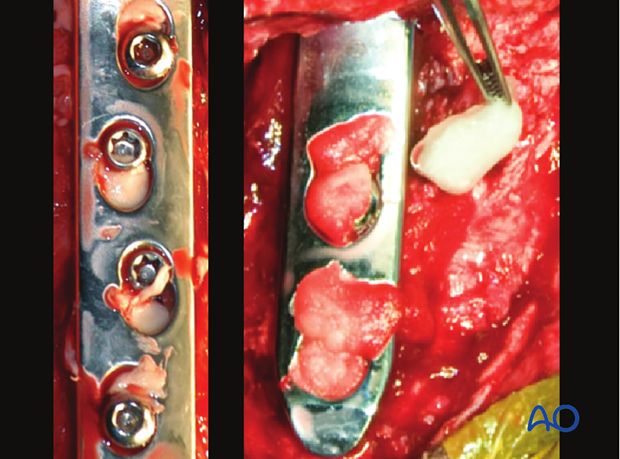

If desired, antibiotic impregnated polymethylmethacrylate (left) or pieces of a collagen sponge (right) can be placed in any voids in the plate.